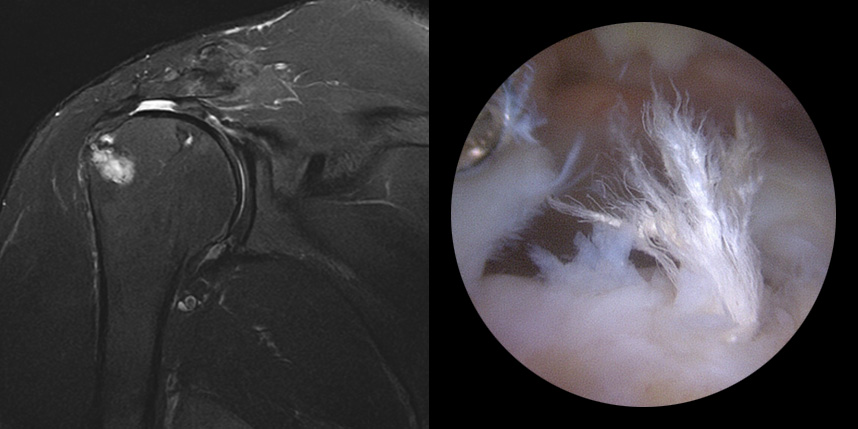

5mm 내외의 최소 절개 후 내시경을

삽입하여 치료 부위를 확인합니다.

의사가 치료 부위를 직접 확인하면서

손상된 조직을 봉합 혹은 제거 합니다.